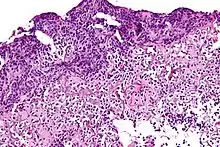

![]() | Dysgerminoma | Dysgerminoma characterized by uniform cells resembling primordial germ cells separated by fibrous septa with lymphocytes. | Category: Histopathology of ovarian dysgerminoma | Ovarian dysgerminoma |